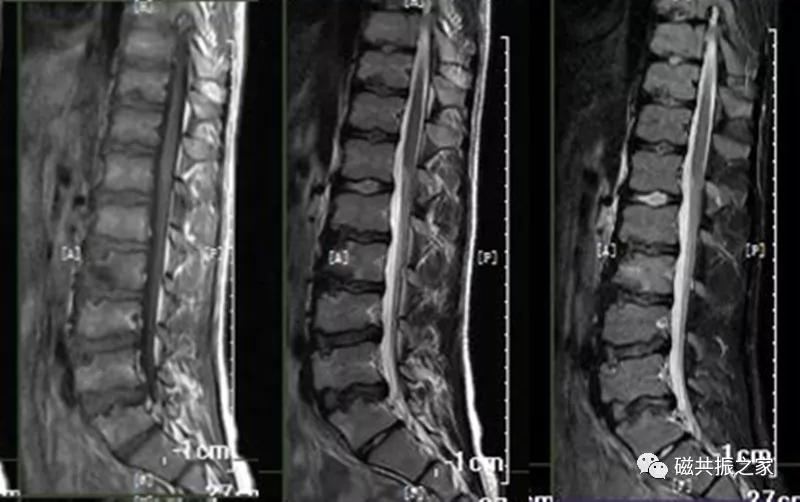

腰椎由5个椎体组成,生理曲度略向前,椎体体积较大,椎体的MR信号与椎体内的骨髓成分相关,椎体内的松质骨主要是脂肪成分,在T1WI上呈中/等信号,在T2WI成高信号;致密的骨皮质在T1WI、T2WI均呈低信号。腰椎常规扫描SAG FSE T1WI、SAG FSE T2WI、SAG STIR,及AX T2WI序列(脊髓内灰质病变可用MEDIC序列,了解神经根可进行稳态进动序列的神经根成像),如脊柱侧弯,椎管占位及了解椎体附件等需加扫冠状位。